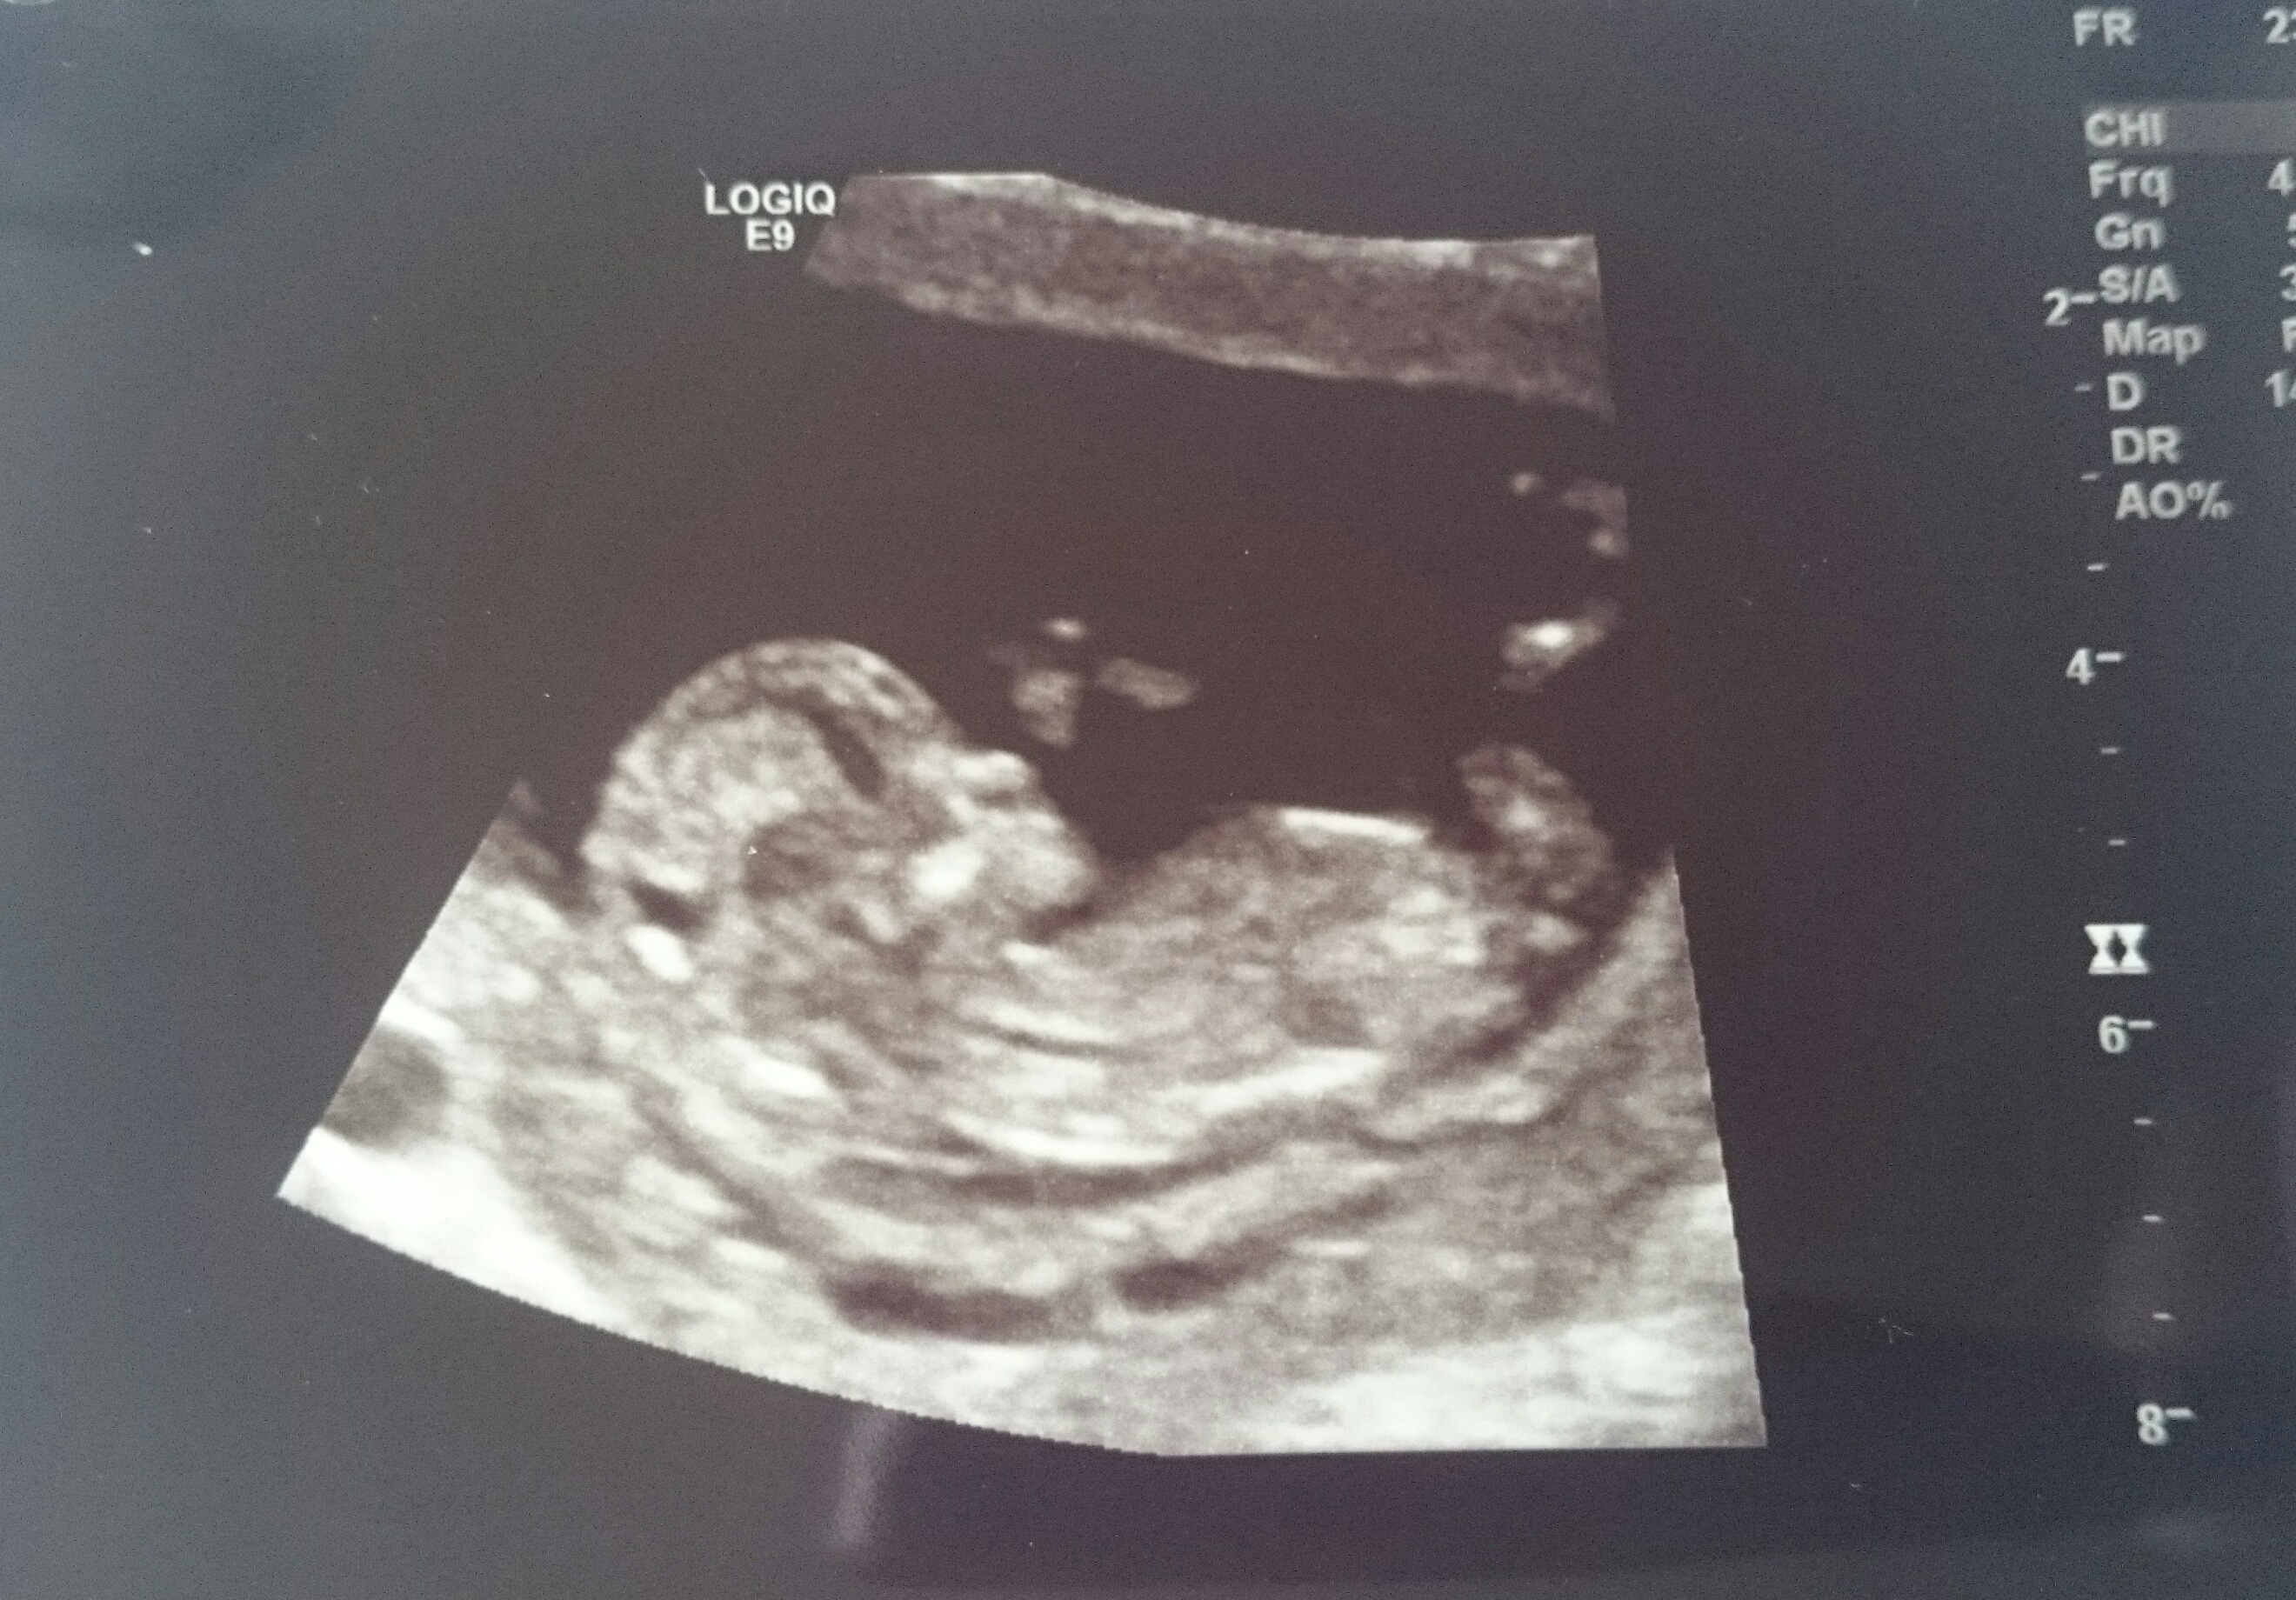

Hi, I don't think I have a nub pic so what would you guess from baby's skull? I know this isn't reliable.... just passing the time under my gender scan :)